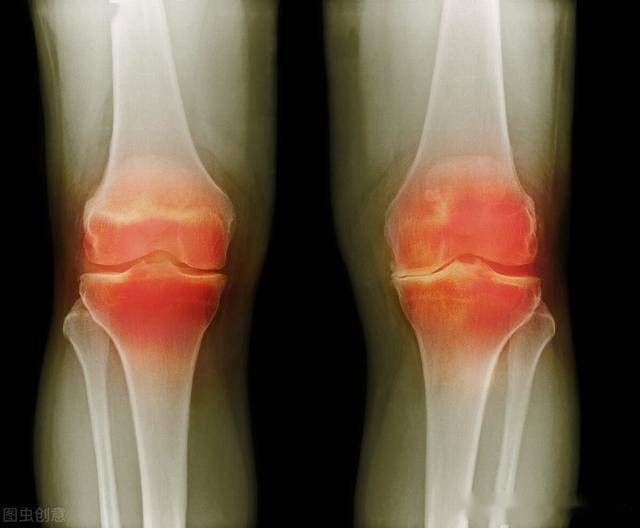

关节对于我们日常生活还是比较重要的,当年纪逐渐上升时,各种关节问题就会逐渐显现出来,很多人到了中老年之后,就很容易出现关节疼痛的现象。

由于年龄的增长,骨骼中的骨质流失变快,就会非常容易导致骨质疏松的出现。尤其对于女性来说,由于更年期的出现,体内激素分泌异常,就更加容易出现骨质疏松的现象。表现出来,就是关节疼痛,除此之外骨质疏松还会增加骨折的风险,所以一定要引起重视。

骨关节炎,就选氨糖

氨糖的作用,主要是补充软骨需要的营养成分,帮助修复软骨组织。不过对于氨糖是否有效这件事来说,有些朋友反馈说有效,但是有些朋友反馈没有效。其实,这个跟每个人的情况有关,因为每个人膝盖疼痛的原因是不一样的。另外,还跟你选的氨糖的成分有关。